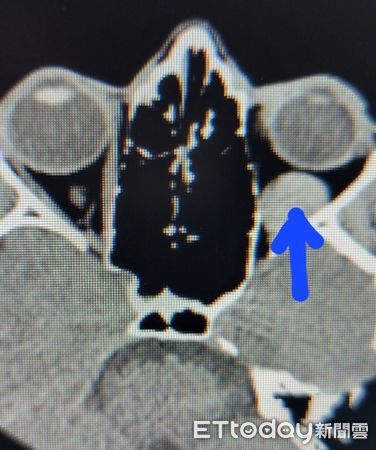

醫師進一步安排陳小姐做頭部與眼眶電腦斷層,發現在軸向視圖,左眼球後方有一塊約5公分的血塊,因此才會壓迫部分眼外肌,眼球肌肉運動受限與稍微影響視神經,導致陳小姐左眼無法正常轉動而形成複視,另外可能輕微壓迫視神經,使視力下降。

幸運的是,血塊沒有明顯壓迫到陳小姐的視神經,否則恐導致失明。經醫師開立降壓、止血藥物,並嚴格叮囑陳小姐別再揉眼睛,3個禮拜後,視力、眼壓都已恢復正常,眼球後的血腫也完全消失,也不再有複視的困擾。

▲經電腦斷層掃描,發現左眼後方還有5公分的血塊。(圖/洪啟庭醫師提供)